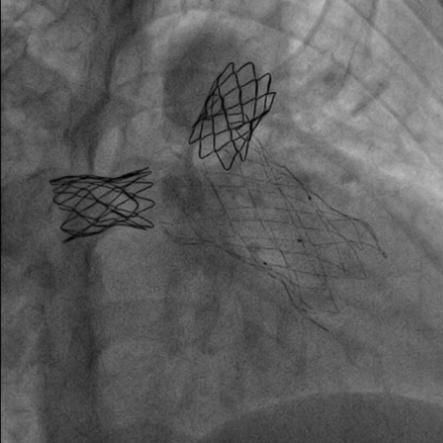

患者在全麻下,首先从左股静脉将造影导管分别送至右心室和肺动脉主干,行造影以明确右室流出道、肺动脉及肺动脉分支的基本情况。同时测量了右室流出道及肺动脉的尺寸。随后输送器通过右侧股静脉延加硬导丝将瓣膜输送到右室流出道,在X线的引导下,将瓣膜精确定位到植入部位并顺利进行瓣膜释放,无反流和瓣周漏,手术效果十分理想。

高主任总结道:本例病例就是在没出现严重肺动脉反流时,先解决了严重的左右肺动脉分支起始部狭窄,不仅促使狭窄远端肺血管的发育,避免了肺动脉分支的闭塞。随着年龄长大,肺动脉反流加剧,右心功能受损时,我们及时植入肺动脉带瓣支架,阻滞了右心功能向失代偿期的发展。